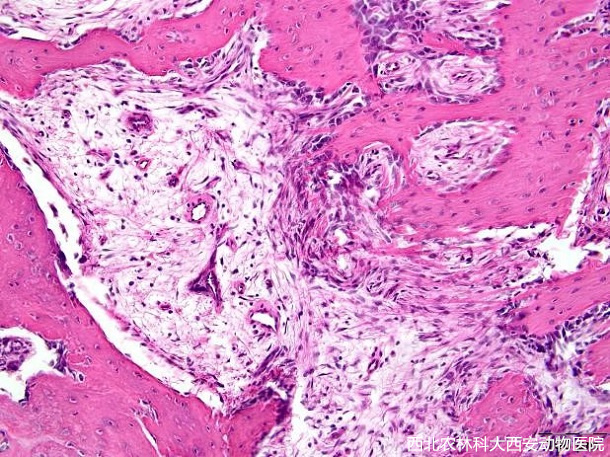

組織病理學(xué)診斷:腹腔囊性異位骨化(heterotopic ossification,HO),伴有出血見(圖4)。

圖四